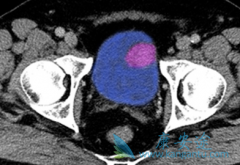

舒尼替尼 (Suninat)已被纳入转移性肾细胞癌(mRCC)一线治疗方案。但是服用舒尼替尼会出现手足综合征、腹痛、腹泻、心肌缺血等不良反应。如何平衡患者的临床获益和治疗带来的慢性毒性是应用舒尼替尼治疗mRCC的最大挑战。一项前瞻的Ⅱ期临床研究,评估 ...

目前,针对晚期肾癌(RCC)靶向药物 舒尼替尼 (索坦)临床试验主要是在西方人群中进行。以往的研究显示,靶向药物相关不良事件(AE)存在种族差异。因此,我们急需更多关于靶向药物在亚洲和中国人群中安全性和有效性的研究数据以更好地指导临床治疗。今 ...

欧狄 沃 (Opdivo)可以治疗晚期肾癌吗?有效率怎么样呢?根据欧狄沃中文说明书,欧狄沃单药,可治疗此前接受过抗血管生成治疗的晚期肾细胞癌患者;联合Yervoy,治疗中等风险或高风险、先前未经治疗的晚期肾癌患者。所以欧狄沃(Opdivo)是治疗晚期肾癌 ...